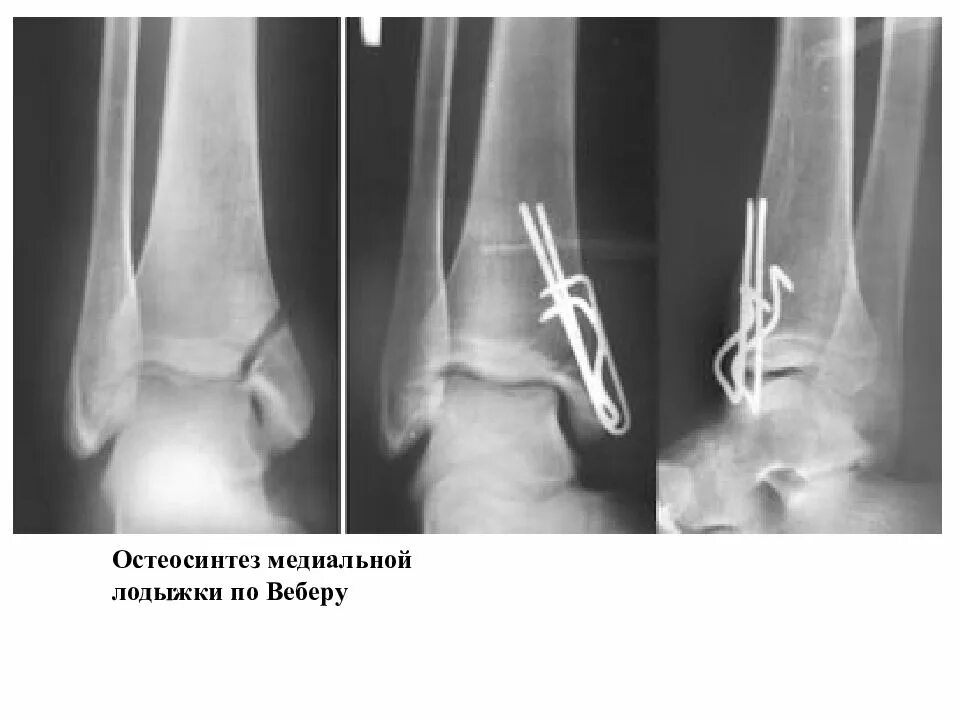

После остеосинтеза лодыжек